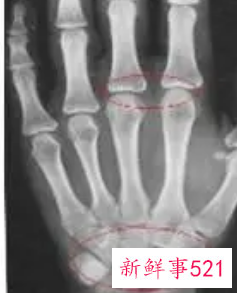

测骨龄对身体是没有危害的,而且价格通常也不会很高,范围在40-100元不等。测骨龄所采用的仪器为X光,用X光机对准儿童的左手腕部进行照射,通过观察左手掌指骨、腕骨及桡尺骨下端的骨化中心的发育程度,来确定骨龄。(让孩子过早玩电脑好不好?有什么危害?)

比较简单的方法就是去拍一个X光,借助于骨骼在X光摄像中的特定图像来确定。通常要拍摄人左手手腕部的X光片,医生通过X光片观察左手掌指骨、腕骨及桡尺骨下端的骨化中心的发育程度,来解读确定骨龄。

测骨龄测哪里

一般手腕部最理想,因为腕关节和手骨骼数目多,骨骺数目多,集中了大量的长骨、短骨和圆骨,且出现和闭合时间跨度大,是观察骨龄的理想部位能够集中地反映了全身骨骼生长和成熟状况。